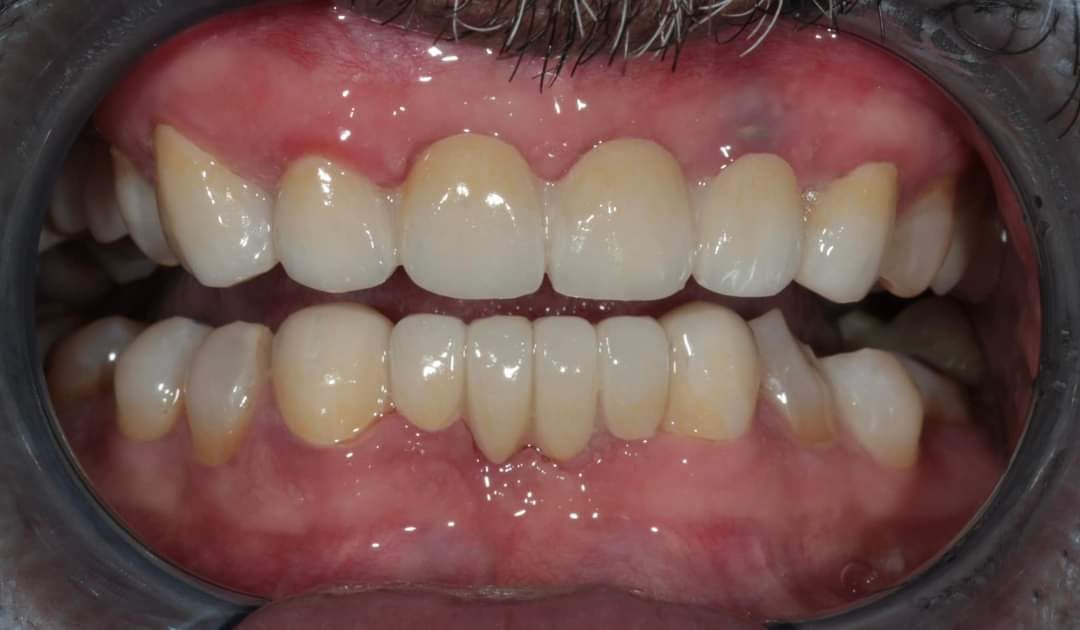

after

Before And After Full MouthRehabilitation Treatment